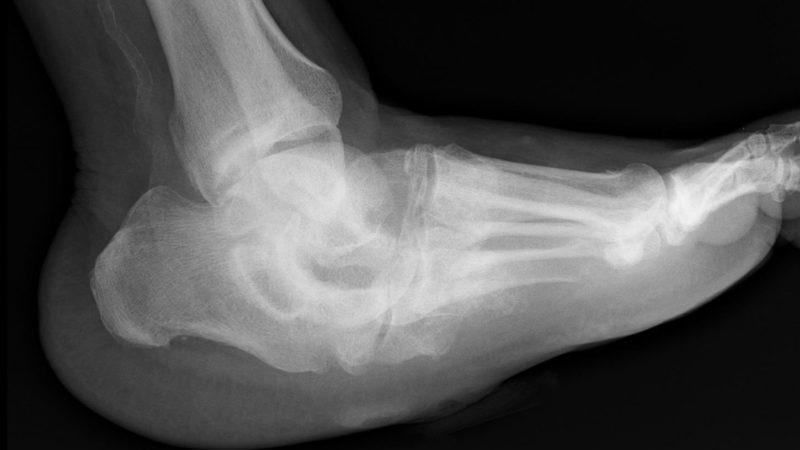

| Деформация стоп и кистей | Изменение формы стоп и кистей, приводящее к деформации суставов. | Ортопедическая обувь, ортезы, оперативное вмешательство в запущенных случаях. |

- деформация стопы, которая начинает напоминать перевернутую бутылку;

Синдром Шарко, также известный как остеоартрит, вызывает множество обсуждений среди пациентов и специалистов. Люди описывают его как болезненное и изнурительное состояние, которое затрагивает суставы, особенно в области стоп и голеностопа. Многие отмечают, что симптомы могут проявляться внезапно, включая отек, покраснение и ограничение подвижности. Важно, что лечение синдрома Шарко требует комплексного подхода. Врачи рекомендуют физиотерапию, чтобы улучшить подвижность и укрепить мышцы вокруг пораженного сустава. Некоторые пациенты также находят облегчение в использовании ортопедических стелек и противовоспалительных препаратов. Однако, как подчеркивают специалисты, ранняя диагностика и индивидуальный подход к лечению играют ключевую роль в успешном управлении этим состоянием. Обсуждения на форумах показывают, что поддержка со стороны сообщества и обмен опытом могут значительно помочь тем, кто сталкивается с этой проблемой.